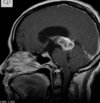

Q

35 anos, Masculino

A

Craniofaringioma adamantinomatoso

26

Criança

Craniofaringioma adamantinomatoso Crianças Lesão suprasselar com componente sólido e cístico; lobulado; calcificação anelar ou nodular presente em quase TODOS os craniofaringeomas pediátricos; Componente cístico proeminente e componente sólido pequeno, mas com realce.